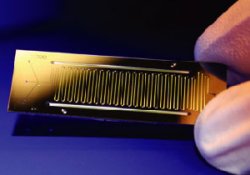

Как и при любом онкологическом заболевании, ранняя диагностика рака молочной железы играет решающую роль для успеха лечения. Ученые из США создали метод, позволяющий без биопсии обнаружить видоизмененные клетки органа до появления симптомов болезни.

Большинство злокачественных опухолей уже в самом начале развития обладают способностью образовывать метастазы в других органах. Наличие в арсенале врачей метода для выявления циркулирующих опухолевых клеток в крови, обеспечит раннюю диагностику рака.